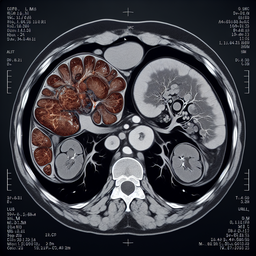

МРТ селезінки (магнітно-резонансна томографія) – це неінвазивний метод візуалізації, який використовують для детального обстеження цього органу. МРТ дозволяє отримати точні зображення тканин без використання рентгенівського випромінювання.

- **Висока точність:** Дає чітке і детальне зображення м'яких тканин.

- **Детальна оцінка:** Може виявити зміни, які не видно на інших видах обстежень, таких як УЗД або КТ.